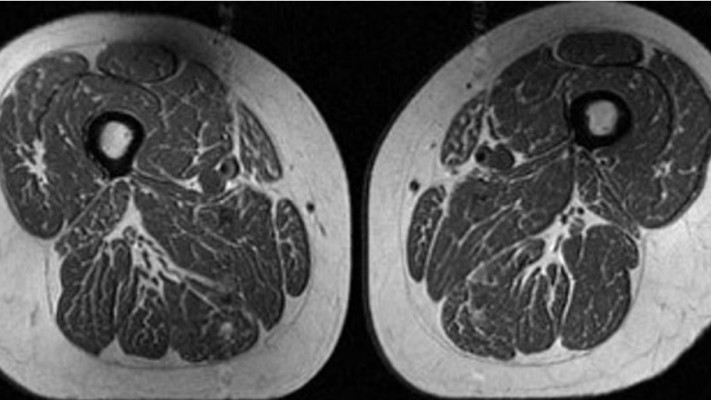

הממצאים הראו שאנשים שצרכו יותר מזון אולטרה מעובד, כמו חטיפים מלוחים, משקאות ממותקים ומזון מהיר, הציגו רמות גבוהות יותר של שומן בין סיבי השריר. מדובר בשומן המכונה שומן בין שרירי, שנוטה להצטבר במצבים של חוסר פעילות או הפרעות מטבוליות. החוקרים הציגו במאמרם את אחת מהדמיות ה-MRI של הירכיים של אחת הנשים שנבדקו. תזונתה כללה 87% מזון אולטרא-מעובד. ההדמיה הראיתה בין סיבי השריר מרבצי שומן רבים.

הדמיית ה-MRI של אחת המשתתפות. מרבצי שומן רבים בין סיבי השריר

הדמיית ה-MRI של אחת המשתתפות. מרבצי שומן רבים בין סיבי השריר | צילום: Radiology journal